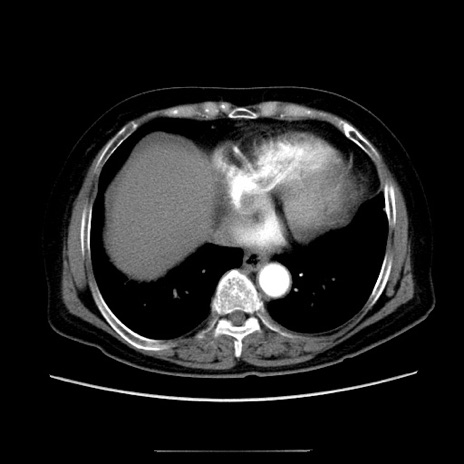

症例5(横断像)

【症例】70歳代女性

【主訴】お腹が張る

【現病歴】1週間くらい前から腹部膨満の自覚あり。昨日夜から増悪したため、本日救急外来受診。

【身体所見】意識清明、BT 36.5℃、BP 165/106mmHg、HR 80bpm、SpO2 98%、腹部:膨満、軟、自発痛・圧痛なし、触診にて不快感あり、腸蠕動音:減弱

【データ】WBC 12600、CRP 1.04